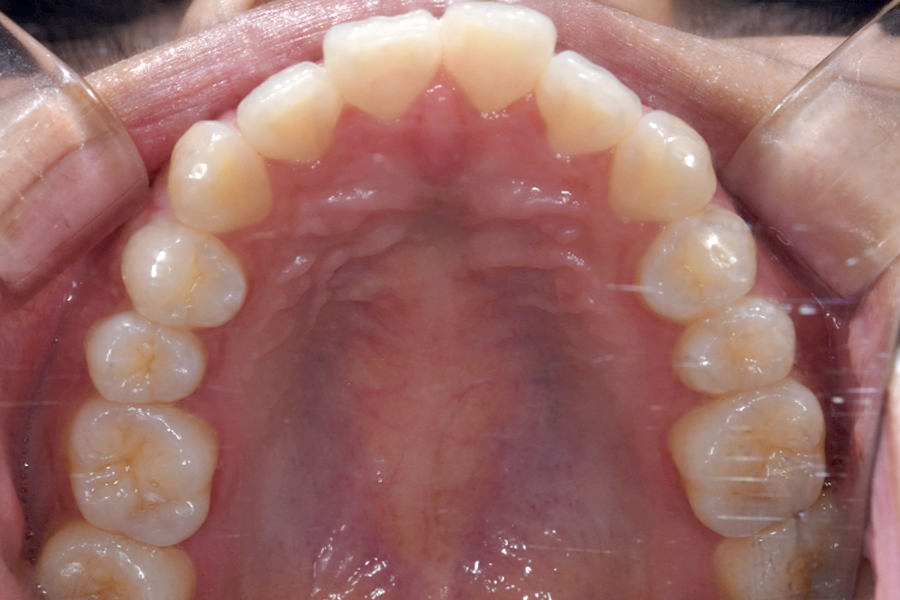

| 主訴 | 歯並びを治したい |

|---|---|

| 治療期間 | 1年9か月 |

| 治療費 | ¥1,023,800(税込) |

| 治療内容 | 目立ちにくいマウスピース矯正(非抜歯矯正) 歯と歯の間に隙間をつくることにより、 歯列弓を広げながら治療を行いました。 |

| 治療のリスク | ・後戻りする可能性があるので リテーナーを最低でも矯正期間以上はつけること ・歯の移動中に、歯の神経が過敏になり冷たいものや熱いものがしみたりする場合があります。 |